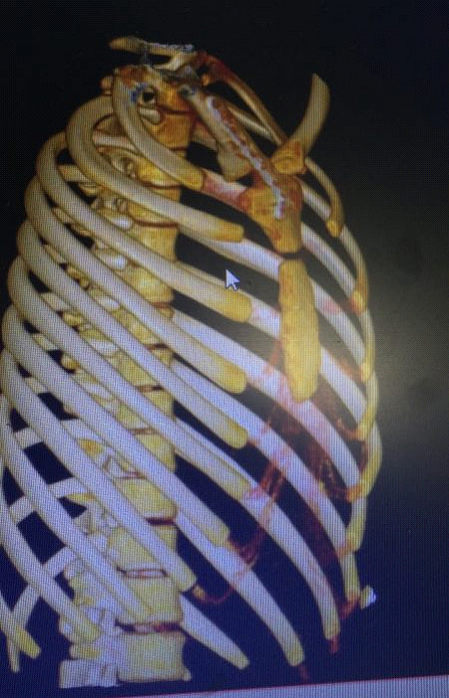

▲CT三维重建显示右胸锁关节后脱位

创伤性胸锁关节脱位仅占肩胛带损伤3%,绝大多数系高能量损伤引起,主要是外伤所致。胸锁关节后脱位时锁骨胸骨端向后方移位,容易压迫上纵膈内重要器官,极少见。胸锁关节后脱位有时是致命的,需要急诊手术复位。